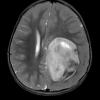

ETMR - Embryonal Tumor Multilayered Rosettes (9)